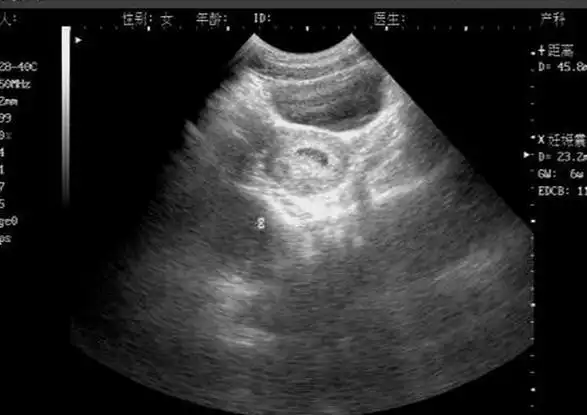

一般情况下,在怀孕40天左右,通过b超检查可看到孕囊大小,孕囊位置

正常情况下,孕30-40天胚胎孕囊形成;孕40-50天,胎芽形成;孕50-60天

孕6周b超产检宝宝还不到1厘米,据说这种长条形孕囊很可能是男生